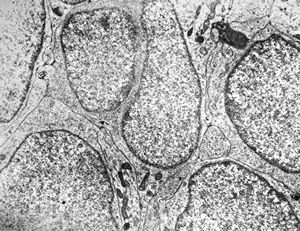

F,49y. | purulent meningitis- meningococcal v.s.